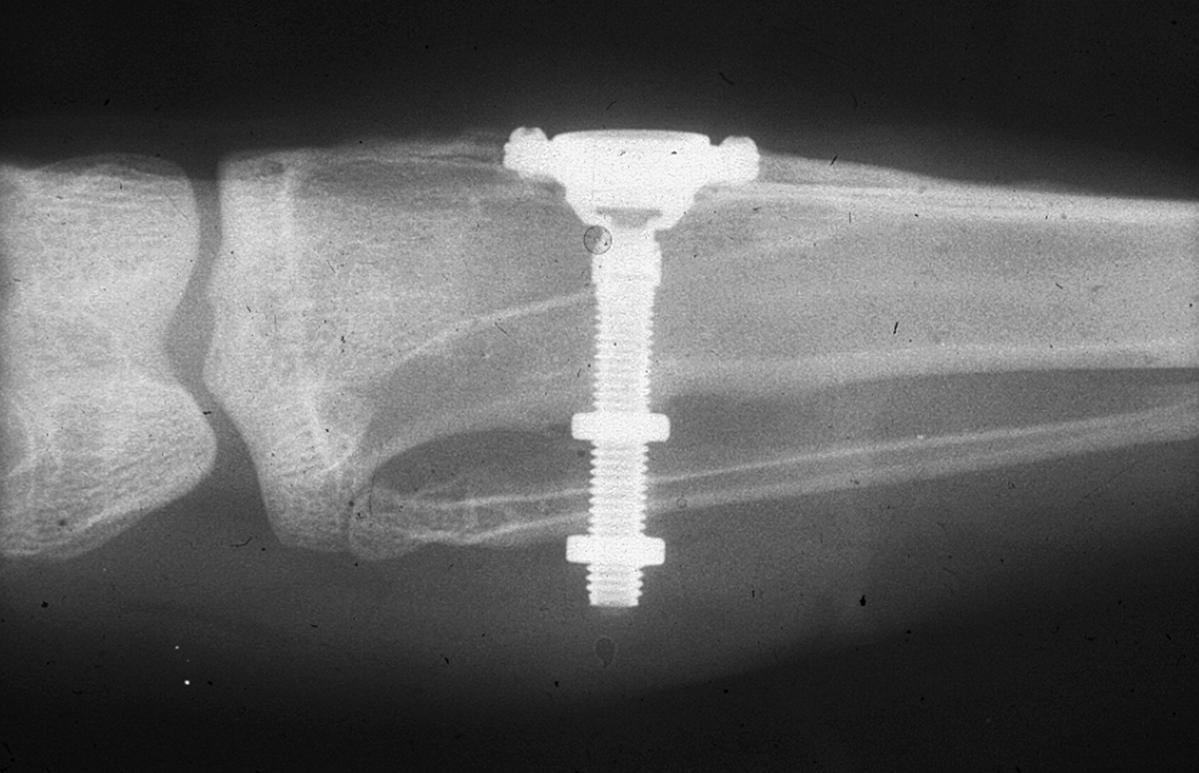

Internal medical equipment like catheters and titanium rods to support broken bones are being used by thousands on a daily basis, and they perform essential life-saving purposes. However, inserting foreign objects into the body does come with some risks, Futurism reports. Chief among them is the blood that tends to clot around the foreign materials, which could cause severe health issues.

Thanks to a new team up between material engineers and biomedical engineers from the Colorado State University, this problem is closer to getting solved. The result of their collaboration is the creation of a surface treatment with “superhemophobic” characteristics. Basically, it creates a coating that will allow materials like titanium to resist blood, thus preventing clotting.

The team published their findings in the Advanced Healthcare Materials magazine. In the paper, the scientists explained how their work could yield significant advancements in creating better medical implants.

“The hemocompatibility of superhemophobic surfaces is investigated and compared with that of hemophobic surfaces and hemophilic surfaces,” the paper’s Abstract reads. “This analysis indicates that only those superhemophobic surfaces with a robust Cassie–Baxter state display significantly lower platelet adhesion and activation. It is envisioned that the understanding gained through this work will lead to the fabrication of improved hemocompatible, superhemophobic medical implants.”

Aside from the considerable difference that the surface brings to preventing blood clots, it also stands to advance the prevention of rejection. Normally, when the body’s immune system detects a foreign object in the body, it activates the defenses in order to fight it off. This leads to inflammation, which has been known to cause death. By applying the surface treatment, the body won’t even know that the foreign object is there.